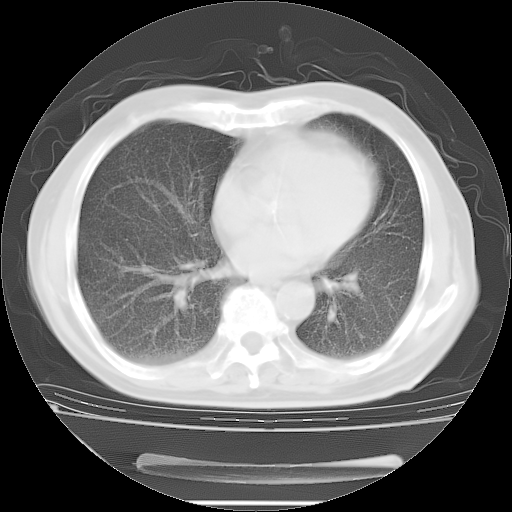

胸腹部CT,诊断意见:左上肺叶钙化灶、左侧胸膜局限性增厚并钙化、胆囊炎。描述部分肺组织呈磨玻璃样改变。